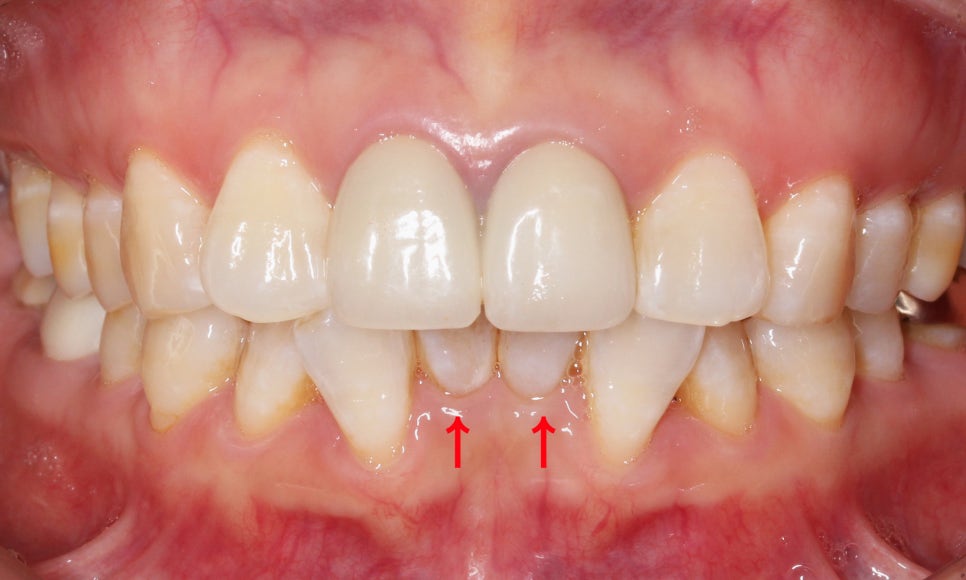

환자분의 아랫니 상태를 보시면

위처럼 앞쪽의 치아들이

심하게 삐뚤거리는 모습인데요,

치아 사이의공간이 좁아서

작은앞니(측절치)의 각도가

심하게 회전된 모습입니다ㅠㅠ